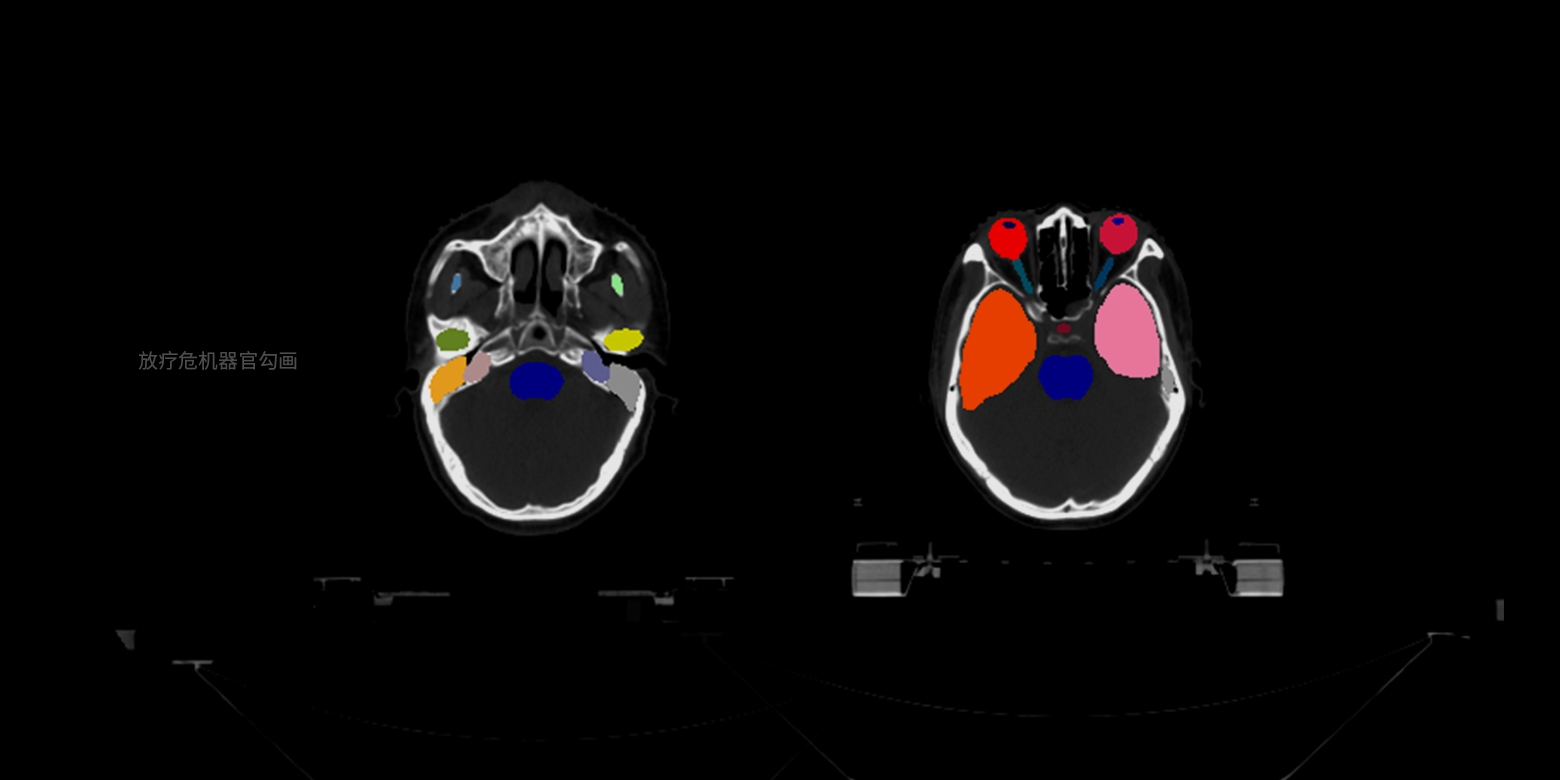

- 02病灶部位的分割與量化

02 / 05

病灶部位的分割與量化

支持針對小樣本的醫學數據進行訓練,實現对多種器官病變提供像素級別的精確圖像分割,並能自動根據關鍵信息進行量化分析和診斷,例如幫助醫生節省人手勾畫放療靶區、分割骨盆腫瘤等,更好的利用時間規劃和為客戶定制化手術。

02 / 05

病灶部位的分割與量化

支持針對小樣本的醫學數據進行訓練,實現对多種器官病變提供像素級別的精確圖像分割,並能自動根據關鍵信息進行量化分析和診斷,例如幫助醫生節省人手勾畫放療靶區、分割骨盆腫瘤等,更好的利用時間規劃和為客戶定制化手術。